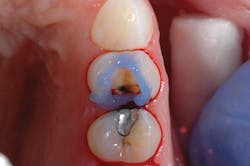

Figure 3: Tooth No. 12 is isolated with the Palodent Plus Sectional Matrix System. Prime&Bond Elect is being scrubbed into the preparation.

After preparing the tooth, a viscous phosphoric acid gel was carefully traced around the margins of the preparation for a selective enamel etching technique and allowed to react for 15 seconds (figure 2). This was followed by copious water rinsing. Isolation was achieved using the Palodent Plus Sectional Matrix System (Dentsply Sirona), and Prime&Bond Elect was scrubbed over the entire preparation of tooth No. 12 followed by a gentle stream of oil-free air for five seconds to thin the material and evaporate the acetone solvent (figure 3).